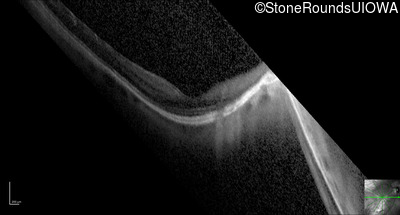

Optical Coherence Tomography - Right - 20/25 -3

Exemplar / OCT Stack